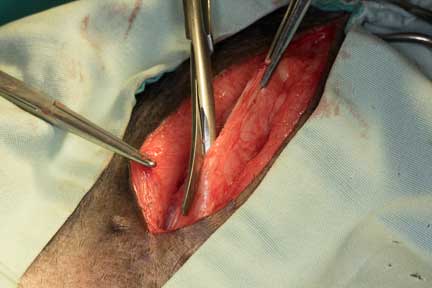

The initial incision is through the skin and into the subcutaneous (SQ) tissue that is covered in fat

A scalpel blad is used to cut through the muscle layer under the SQ tissue

The scalpel cuts into a specific area of the muscle called the linea alba. This is a tendinous attachment between the muscles that is used to suture the muscles back at the end of the surgery.

The incision is extended with a scissor